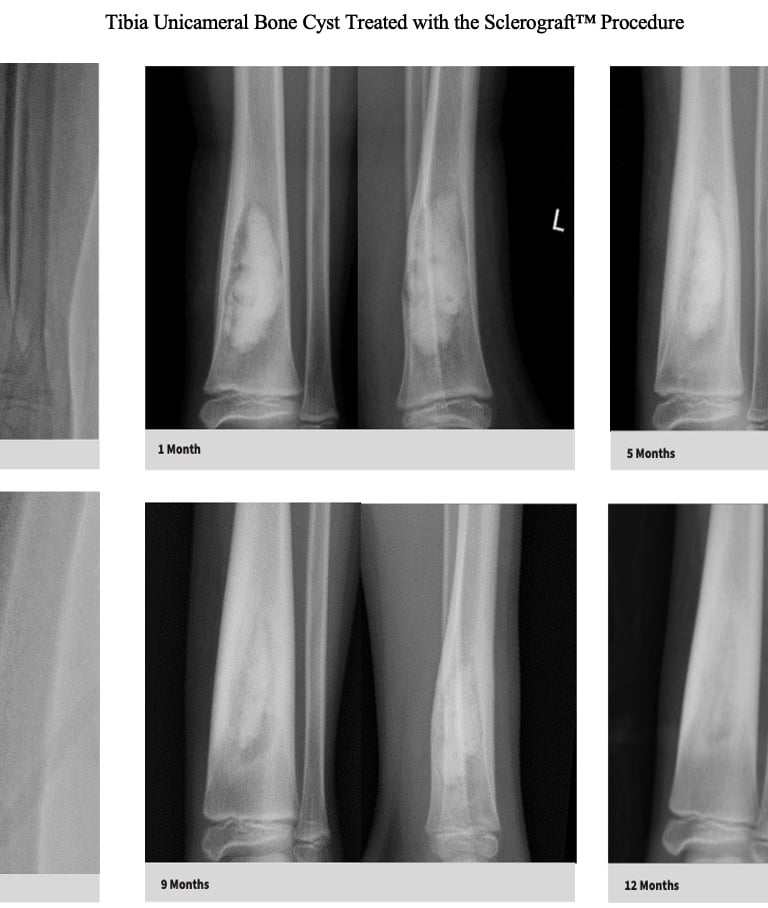

Utilizing needles, chemical sclerosis destroys the cyst wall and regenerative bone graft is injected via the needles to expedite bone healing.

The doctor uses imaging guidance (like X-ray or ultrasound) to guide needles into the cyst.

Chemical sclerosis using chemicals like doxycycline are washed through the cyst to kill the cyst wall lining

Regenerative bone graft is then injected through the needles and the needles are removed. The bone graft is temporary and is eventually reabsorbed by the body.

Quick recovery and bone formation seen between 6 weeks to 3 months

Proven success in both UBCs and ABCs

Bone thickening begins to occur after approximately 6 weeks, so if you child is in a sling or uses crutches, that will be continued until the first x-ray is obtained.

Follow-up imaging is usually obtained at 6 weeks, 3 months, 6 months, 12 months and annually for at least 3 years.

The decision to return to normal physical activity is driven by how well the bone has healed based on the follow-up x-rays.

The long term follow-up with x-rays is critical because of the possibility of bone cyst recurrence. Generally, if a recurrence occurs, it tends to be noticeable by the 6 month mark

Gallery

Explore our educational resources and images